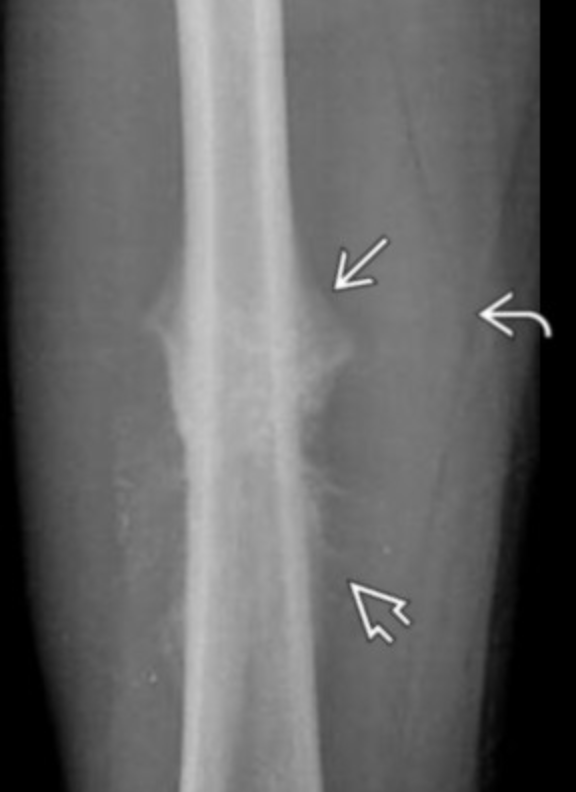

Classic Osteosarcoma

• Age 10-20 yo

• Osteoid matrix (cloud like)

• Metaphysis typically

• Femur and humerus typically

• Skip lesions

• Mets within the bone